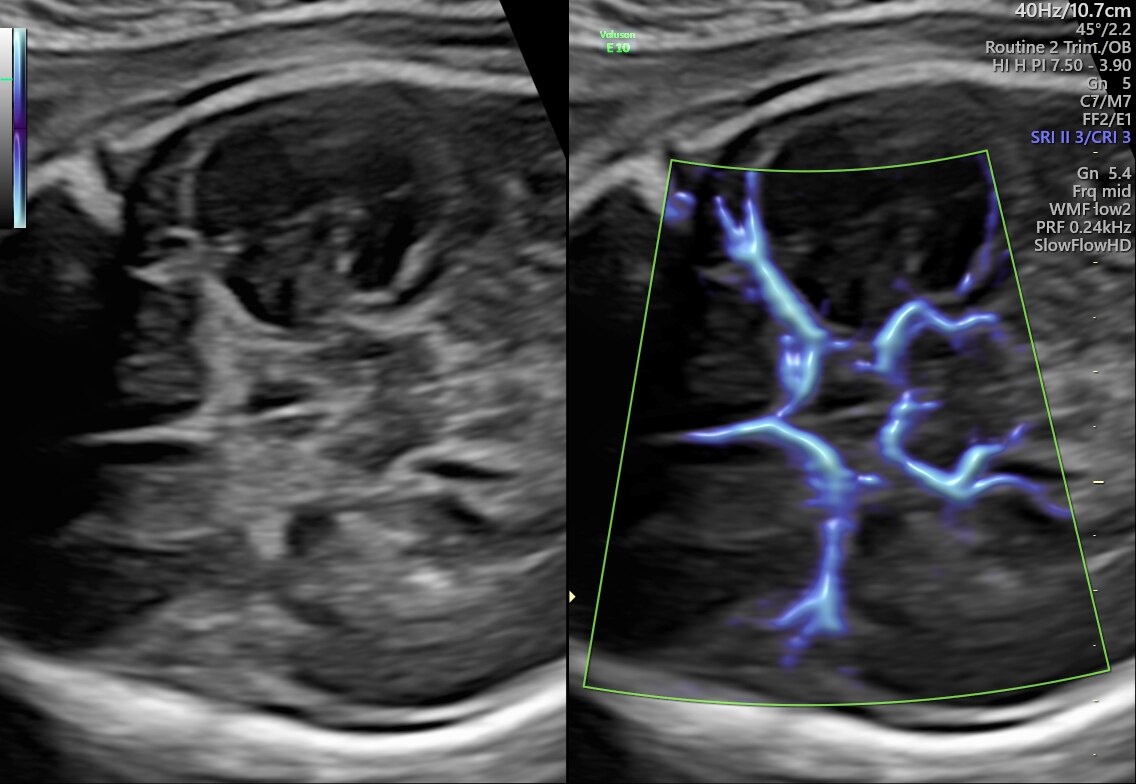

15-week fetal circulatory system with eSTIC and HD-Flow™